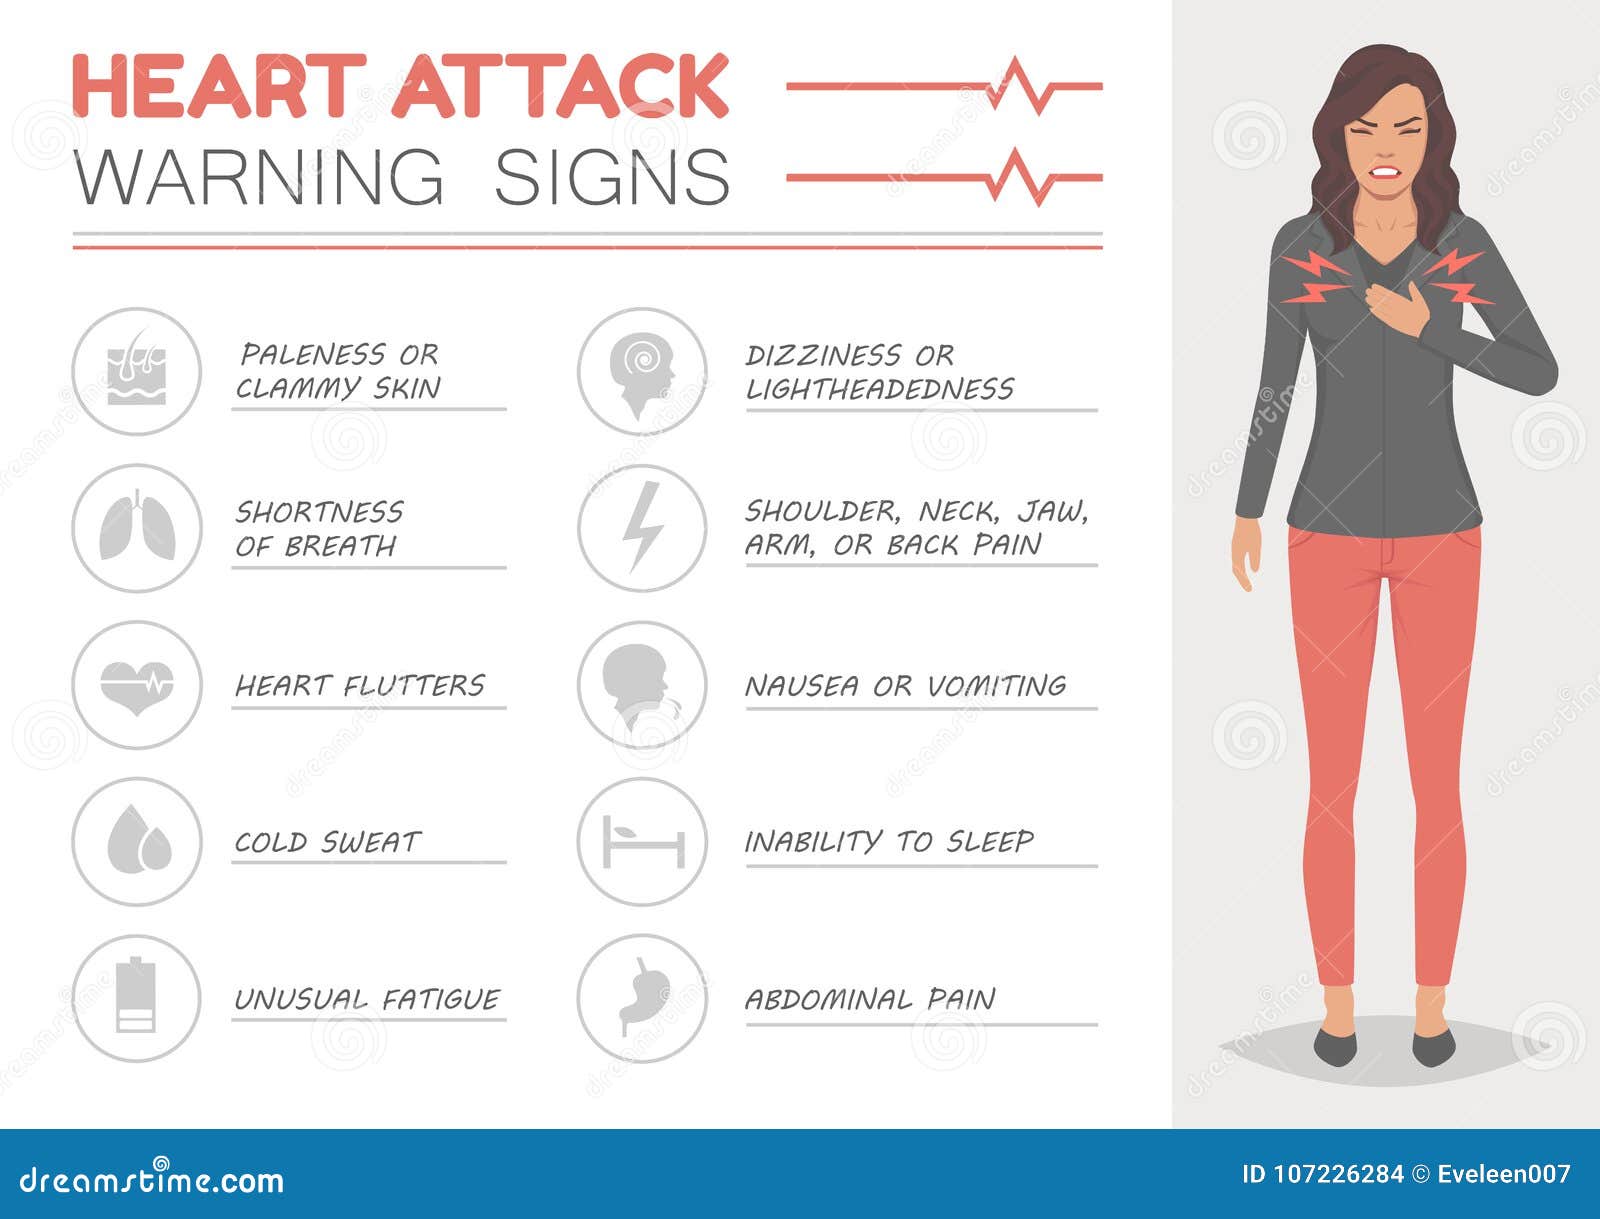

Heart Attack Woman Disease Symptoms Medical Illustration

Heart Attack Woman Disease Symptoms Medical Illustration

It Is Common Knowledge That The Symptoms Of Heart Attack Can Be

Heart Attack Symptoms

Heart Attack Signs And Symptoms